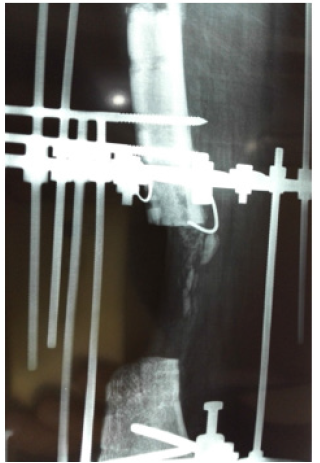

A fifty years old smoker had a history of motor vehicle accident and fracture of femur that was fixed with plate and screws. The plate was broken and was removed and intramedullary nail was put in with iliac crest bone graft. It became infected and was removed. Then uniplanar external fixator was applied but neither infection control nor union achieved. After three years of the initial trauma the patient again present to us for the same problem. Initially we stopped all medicines and stressed the patient for cession of smoking. After three months of cession of smoking, We applied Ilizarov fixator did proximal corticotomy for transport and removed the dead ends till bleeding ends which created a gap of 6 centimeter. After one month of transport there was sever pain while rotating the nuts. When we did radiographs, we saw callus formation in front of transport segment. we stopped the transport and advise the patient for active exercises and regular follow up at one month interval after six month the gap was filled and bone healed without any intervention.